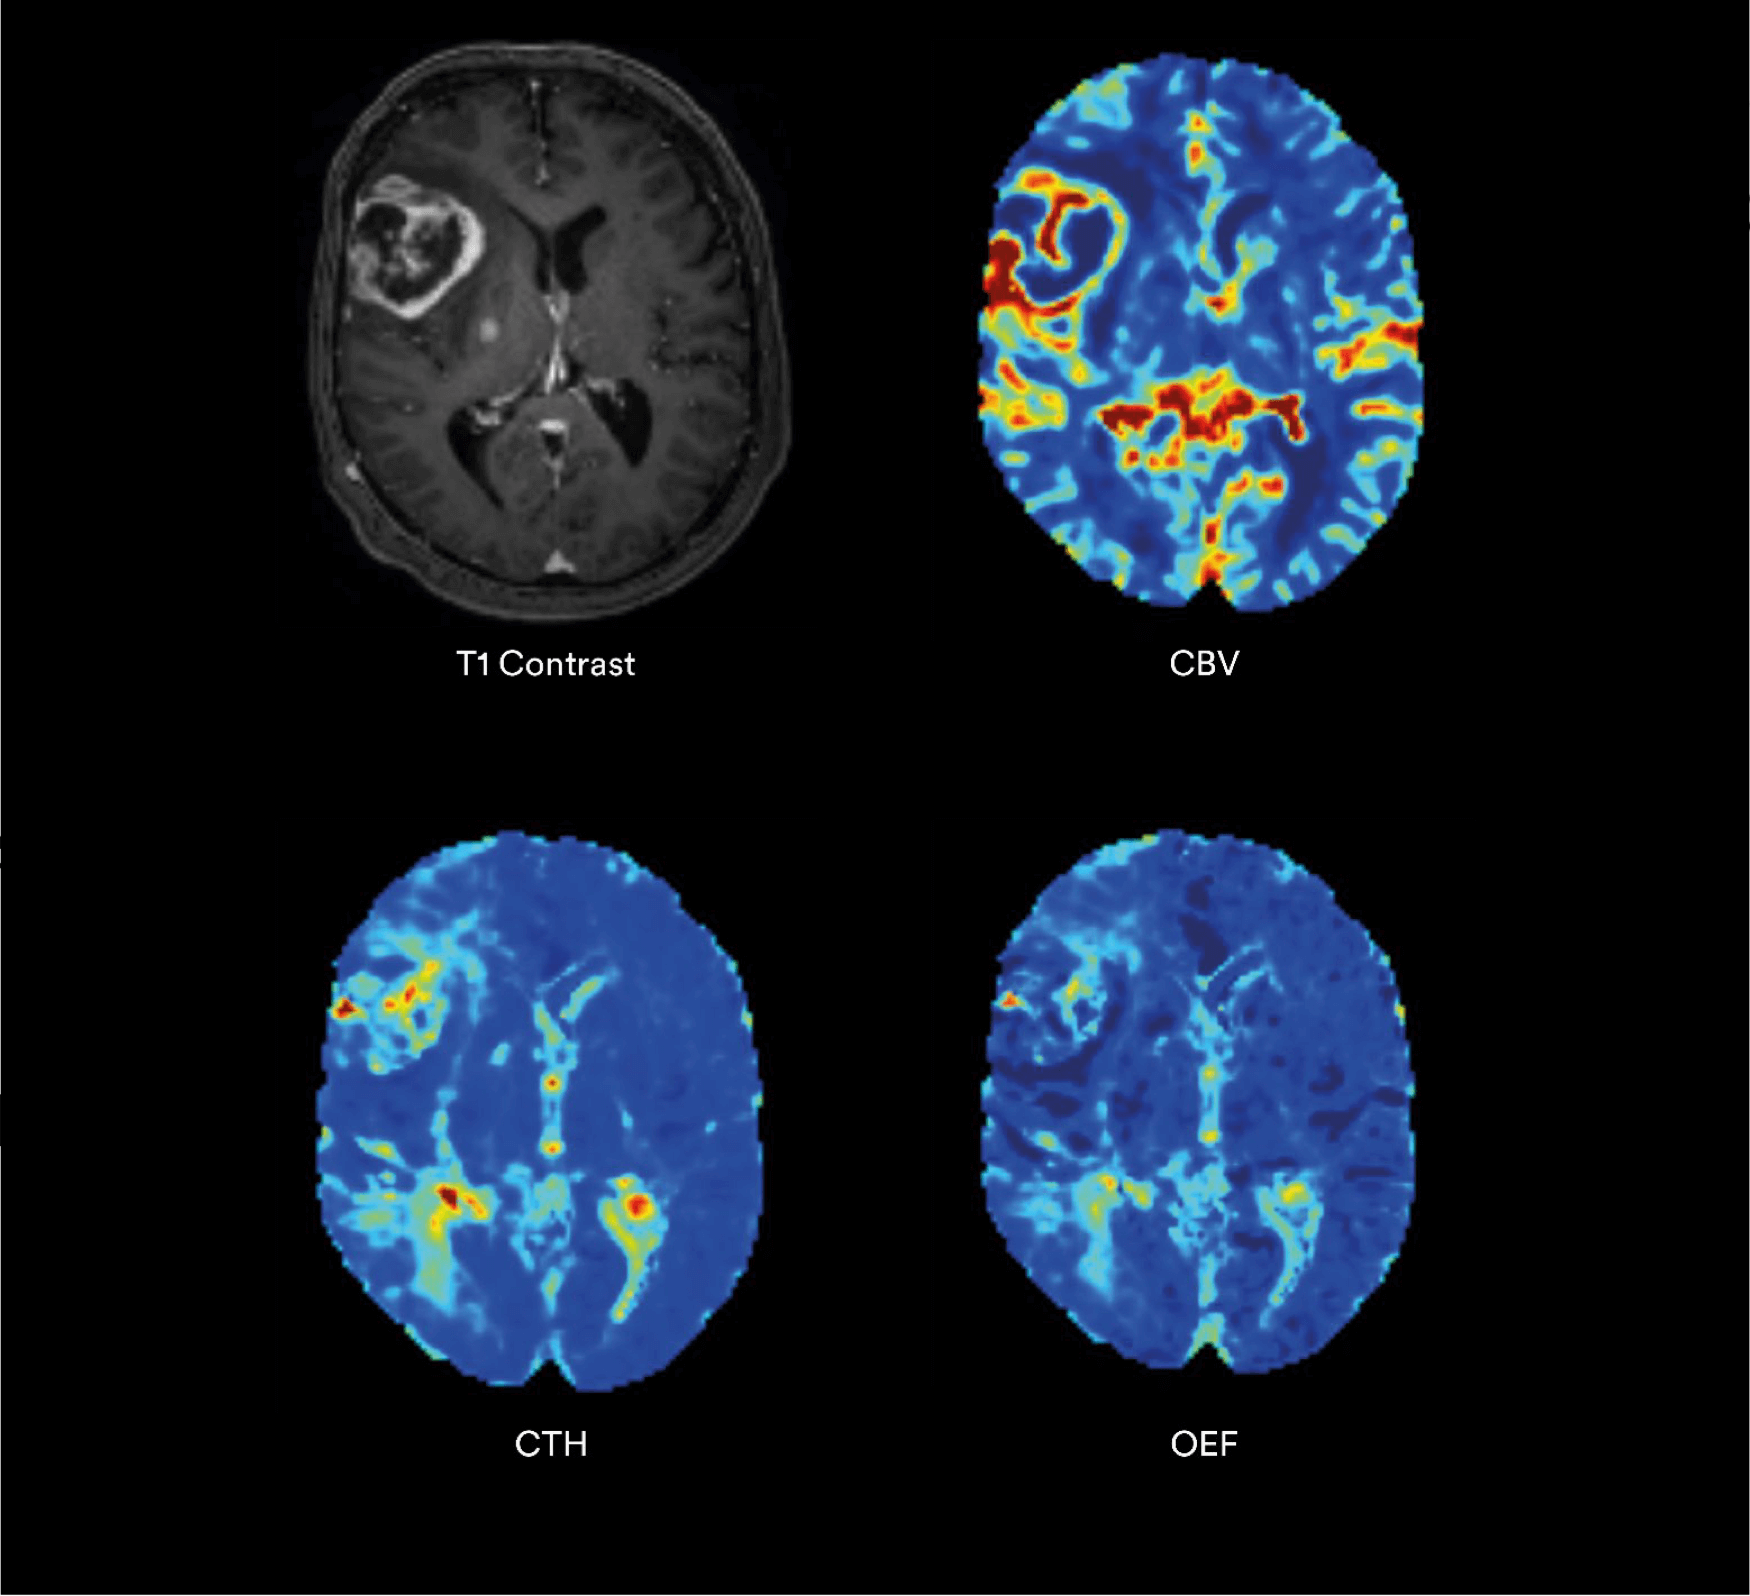

Biomarcatori Metabolici

- OEF Frazione di estrazione dell’ossigeno.

- CMRO₂ Tasso metabolico di consumo dell’ossigeno.

Il Modello Vascolare: un nuovo standard di valutazione

Il Vascular Model (VM) sviluppato da Cercare Medical è un componente chiave di tutte le soluzioni Stroke.

Rispetto ai modelli tradizionali, il VM offre:

- una visualizzazione più chiara delle aree ipoperfuse,

- una migliore correlazione con l’infarto finale,

- una maggiore coerenza con i deficit neurologici reali del paziente.